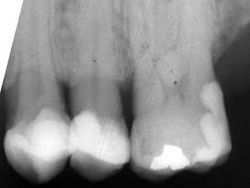

Beachte: Die Fraktur verläuft mesial 2 mm weit durch eine initiale Karies, zentral 6 mm neben einer Amalgamfüllung, und distal 3 mm lang mitten durch eine intakte Kompositfüllung. Diese ist mittig gespalten, aber nirgends vom Zahn abgerissen. Das Zentrum der Amalgamfüllung ist nicht gespalten.

Der Patient ist ein Heavy biter und kam seit Jahren immer wieder mal um Hyperbalancen einzuschleifen. Zudem war dieser +6 der letzte Molar links oben.

Auch auf diesem Röntgenbild ist weder die Hyperbalance noch der kleine Höckerwinkel mit der vertieften Zentrik sichtbar. Die initiale Karies war klinisch nicht sichtbar.